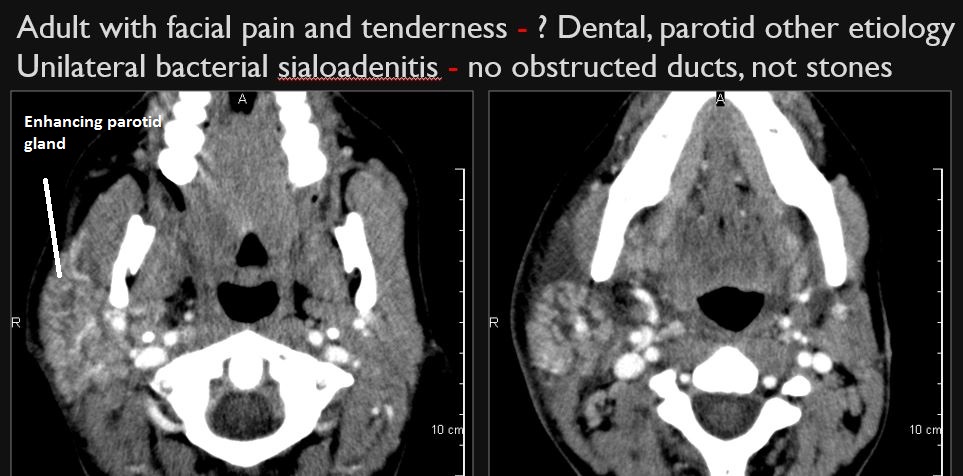

Parotid Glands

There is a developing abscess within the parotid gland.

The parotid ducts and/or intraglandular ductal systems are dilated and/or with evidence of intraductal stones other causes of obstruction.

There is edema (cellulitis) and/or abscess within the fat surrounding the parotid gland and/or of the masticator space or other adjacent spaces.